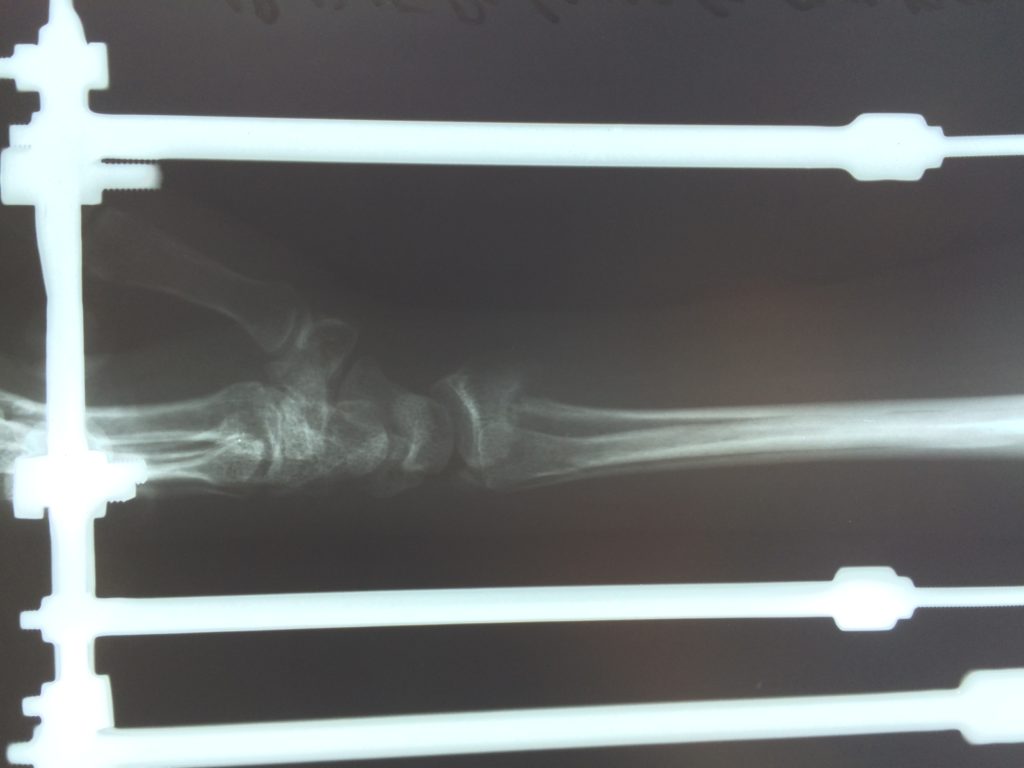

Операция - открытая репозиция, остеосинтез лучевой кости пластиной с костной ксенопластикой материалом "Остеоматрикс". На контрольных снимках в три месяца имеется консолидация перелома, миграции фиксатора нет, имеется остеоинтеграция ксенопластического материала.

Отдаленные результаты через 3 (три) месяца: